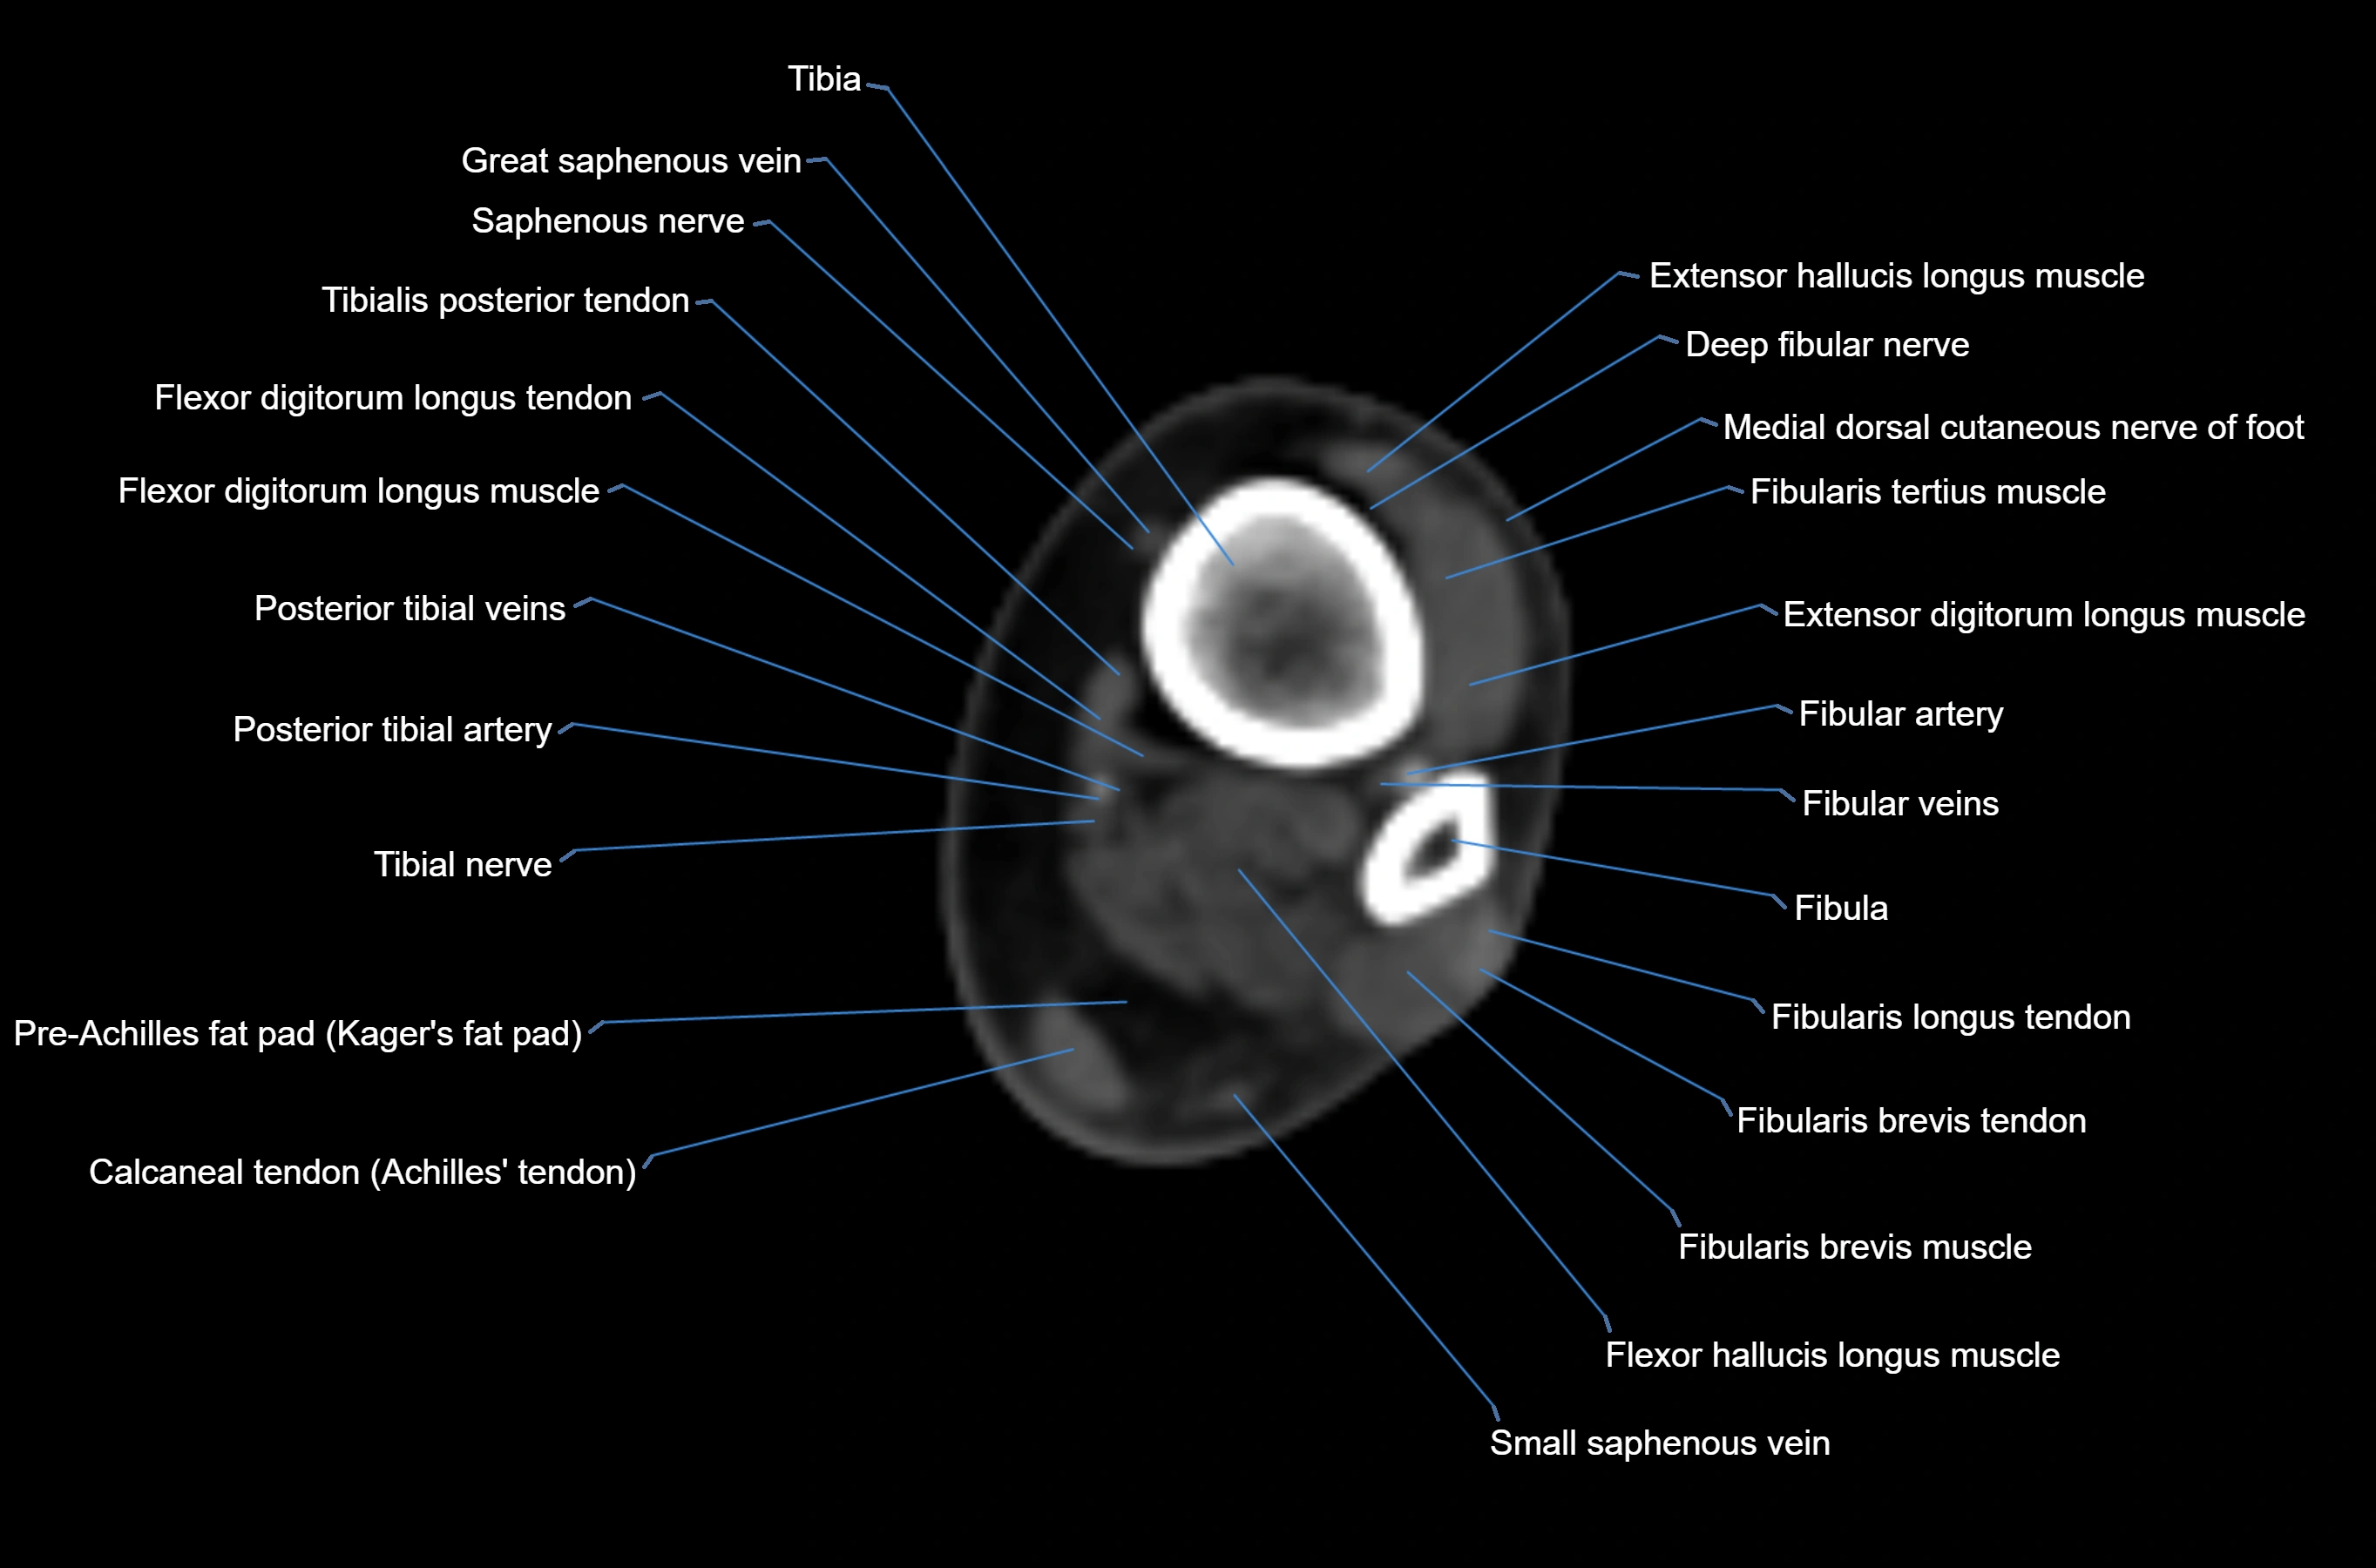

MRI image